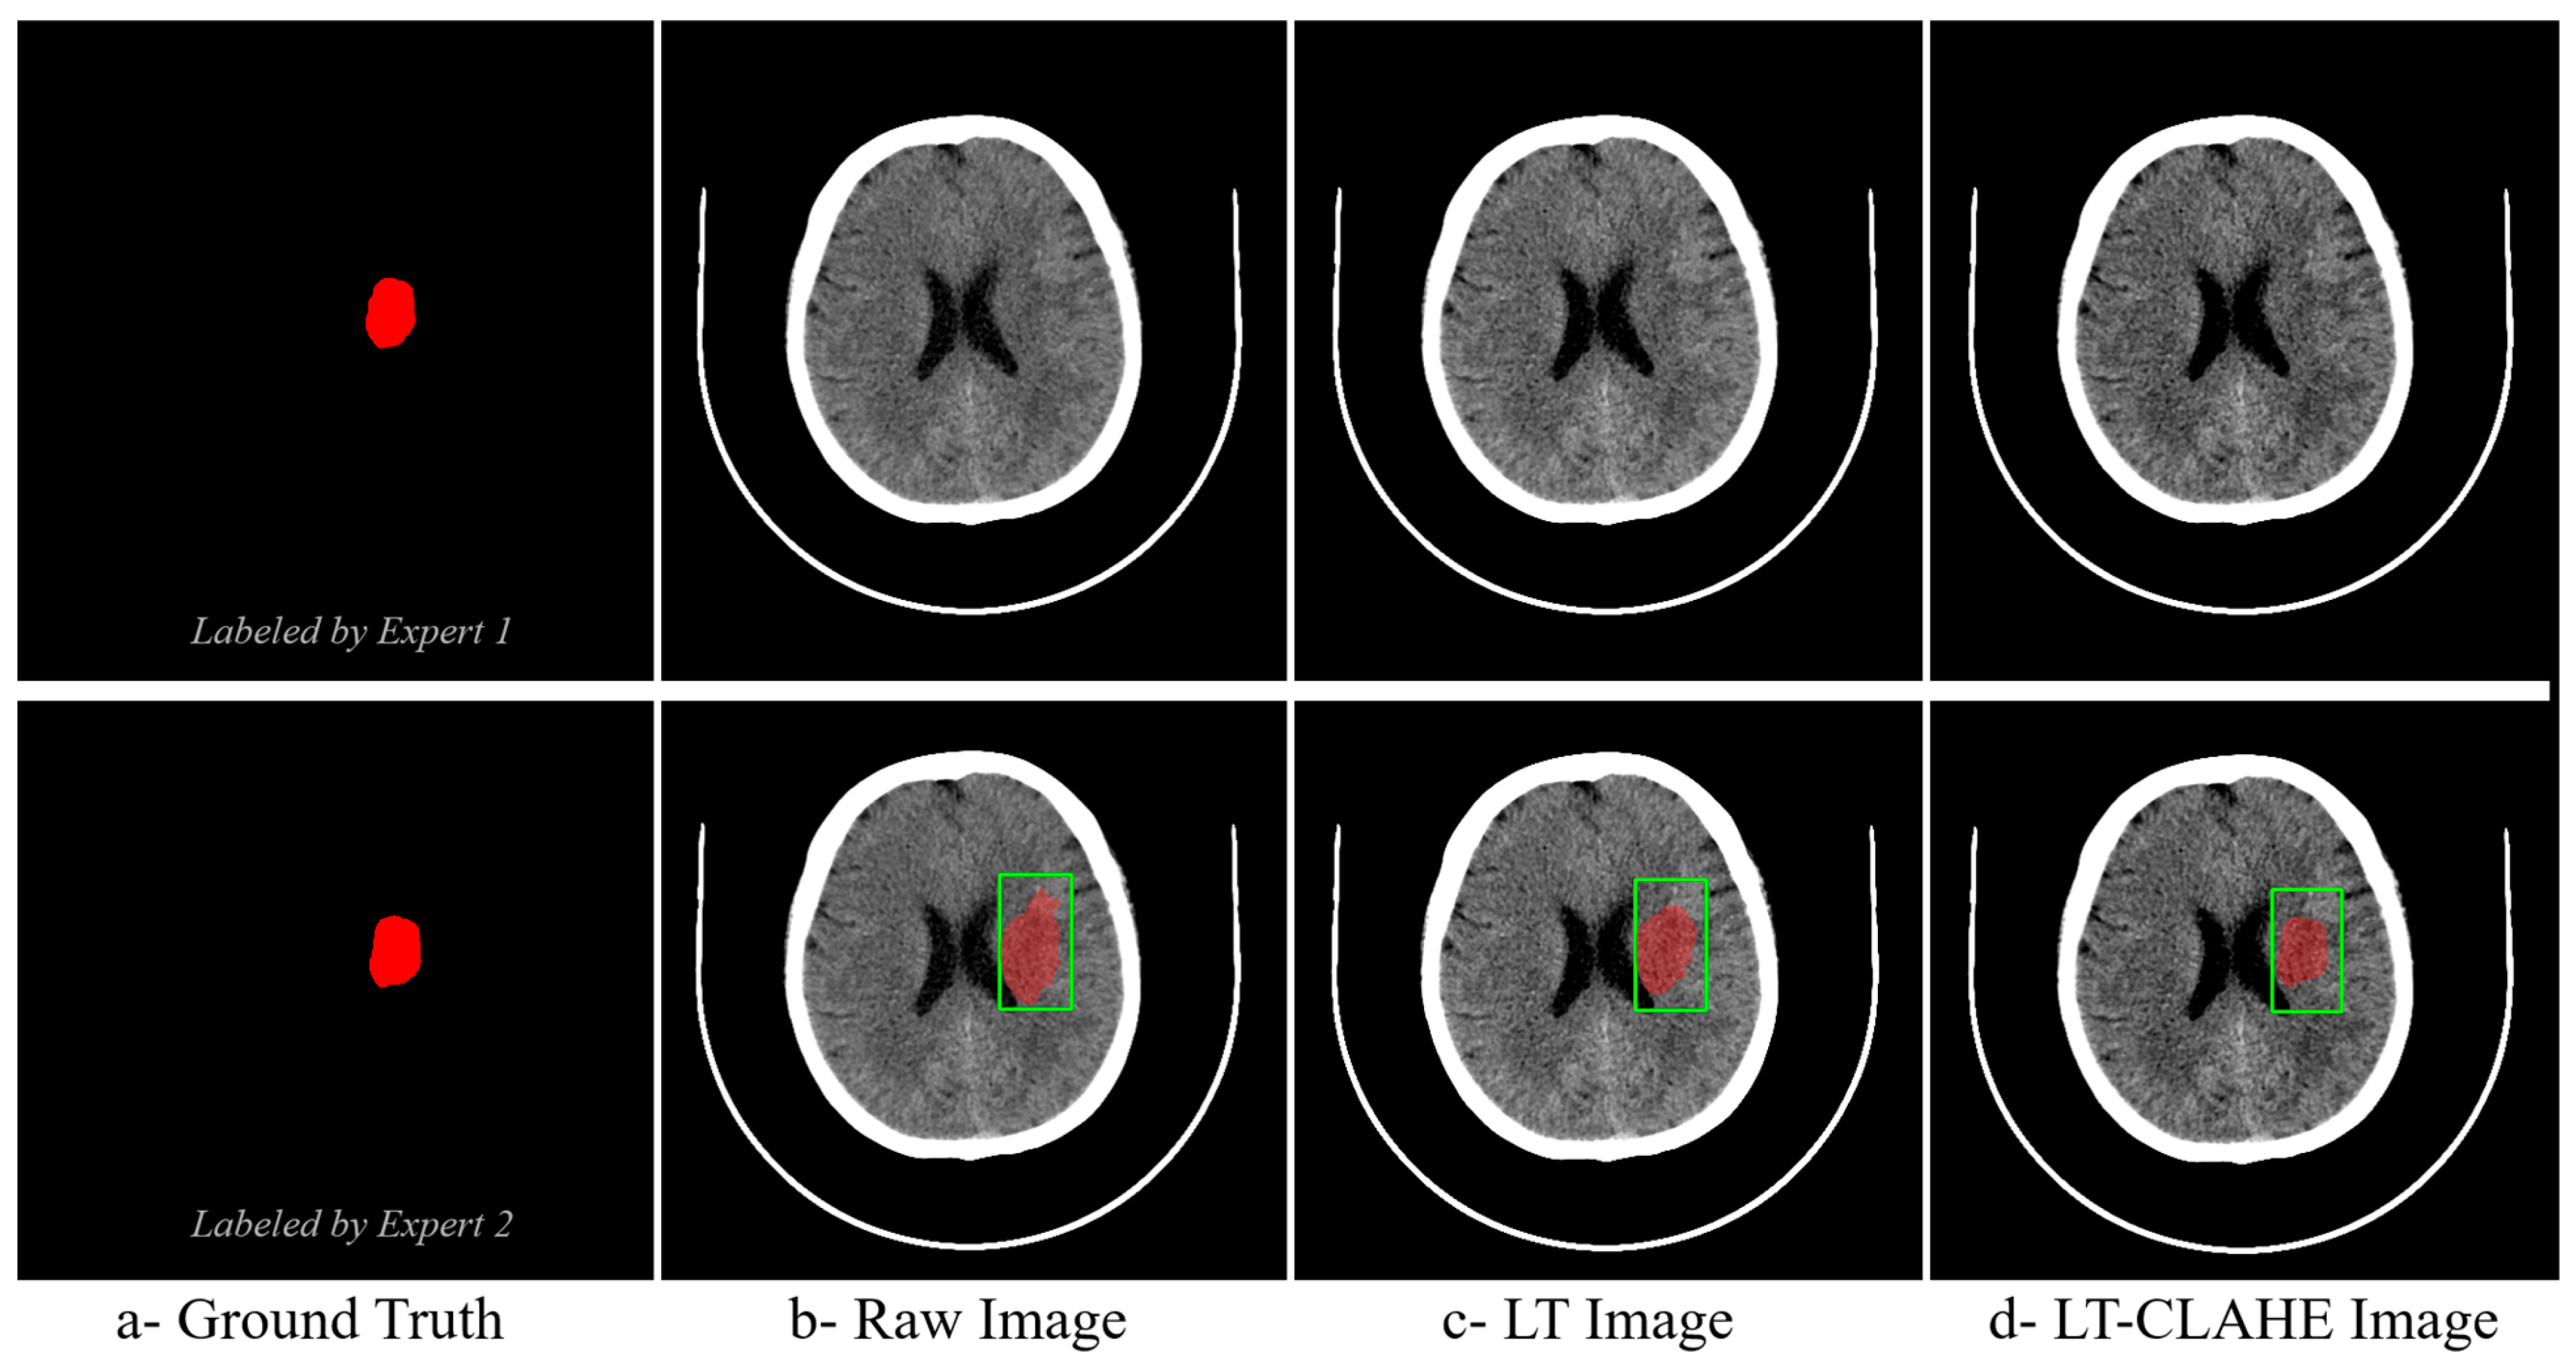

The effectiveness of neural network-optimized enhancement is clearly demonstrated through visual comparison. Figure 4 presents a representative hyperacute stroke case showing expert ground truth annotations from two independent radiologists alongside the same case processed as (b) raw image, (c) deep linear transformation (LT), and (d) combined deep LT-CLAHE enhancement. The progressive improvement in lesion visibility and contrast is evident across the enhancement methods, with the LT-CLAHE approach providing the clearest delineation of the subtle hypodense region identified by both experts. This visual enhancement directly correlates with the improved classification accuracies observed in the quantitative analysis, demonstrating how neural network optimization enhances detection of challenging hyperacute stroke lesions.

The visual comparison in Figure 4 demonstrates the practical effect of neural network–optimized enhancement on hyperacute stroke detection. Relative to the raw image and the image processed with deep linear transformation alone, the combined deep LT–CLAHE output provides the clearest delineation of the subtle hypodense region identified independently by two radiologists. This qualitative improvement is concordant with the quantitative gains observed in classification accuracy, particularly in the hyperacute phase where lesion conspicuity is lowest. The finding is consistent with prior reports that careful intensity manipulation improves early ischemic detection on non-contrast CT, provided contrast is increased without amplifying noise [13]. Our data extend these observations by showing that learned, image-adaptive parameters deliver this balance more reliably than fixed settings.

Figure 4. Visual Comparison of Enhancement Methods for Hyperacute Stroke Detection with Expert Ground Truth Annotations. The green square denotes the clinically suspected region of interest (ROI). The red overlay is the delineated/segmented lesion.